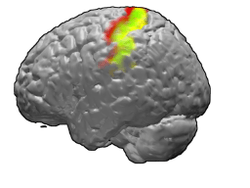

Brodmann areas 3, 1 and 2 of human brain. Brodmann area 3 is in red, area 1 in green, and area 2 in yellow. | |

Brodmann areas 3, 1 and 2

Brodmann areas 3, 1, and 2 make up the primary somatosensory cortex of the human brain (or S1). Because Brodmann sliced the brain somewhat obliquely, he encountered area 1 first; however, from anterior to posterior, the Brodmann designations are 3, 1, and 2, respectively.

Brodmann area (BA) 3 is subdivided into areas 3a and 3b. Where BA 1 occupies the apex of the postcentral gyrus, the rostral border of BA 3a is in the nadir of the Central sulcus, and is caudally followed by BA 3b, then BA 1, with BA 2 following and ending in the nadir of the postcentral sulcus. BA 3b is now conceived as the primary somatosensory cortex because 1) it receives dense inputs from the NP nucleus of the thalamus; 2) its neurons are highly responsive to somatosensory stimuli, but not other stimuli; 3) lesions here impair somatic sensation; and 4) electrical stimulation evokes somatic sensory experience. BA 3a also receives dense input from the thalamus; however, this area is concerned with proprioception.

Areas 1 and 2 receive dense inputs from BA 3b. The projection from 3b to 1 primarily relays texture information; the projection to area 2 emphasizes size and shape. Lesions confined to these areas produce predictable dysfunction in texture, size, and shape discrimination.

The positions of Brodmann areas 3, 1, and 2 are - from the nadir of the central sulcus toward the apex of the postcentral gyrus - 3a, 3b, 1, and 2, respectively.